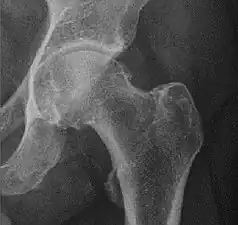

X-ray of hip dysplasia